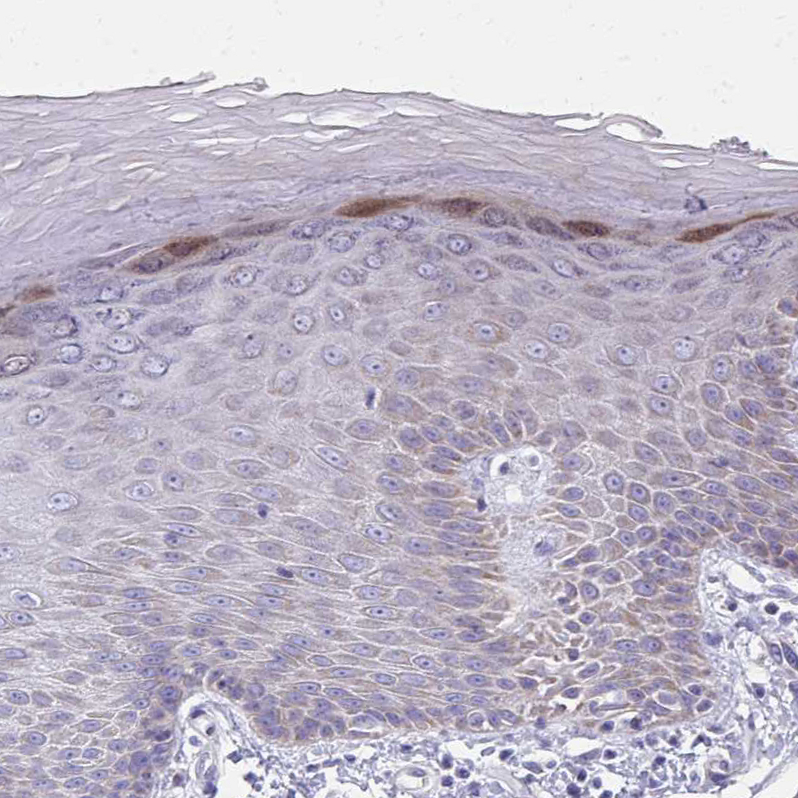

Immunohistochemical staining of human skin shows moderate cytoplasmic positivity in keratinocytes in stratum granulosum.